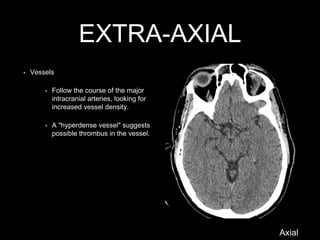

• Vessels

• Follow the course of the major

intracranial arteries, looking for

increased vessel density.

• A "hyperdense vessel" suggests

possible thrombus in the vessel.